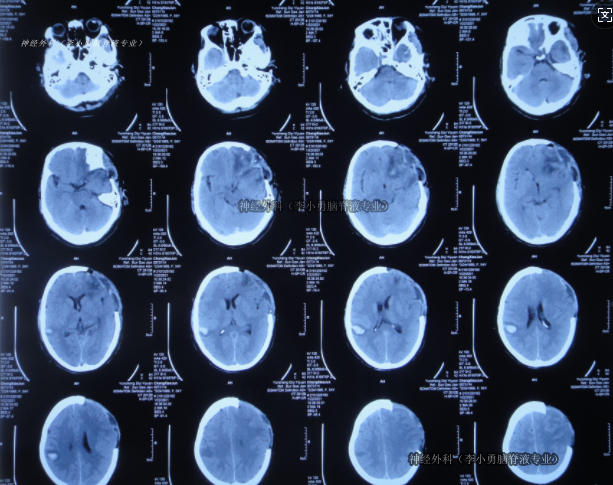

左额叶-胼胝体肿瘤卒中 侵犯对侧额叶 急诊开颅切除 镜下全切

卢云鹤 关注

上海蓝十字脑科医院/同济大学附属脑科医院前天10:07 76阅读 0评论 1点赞 -